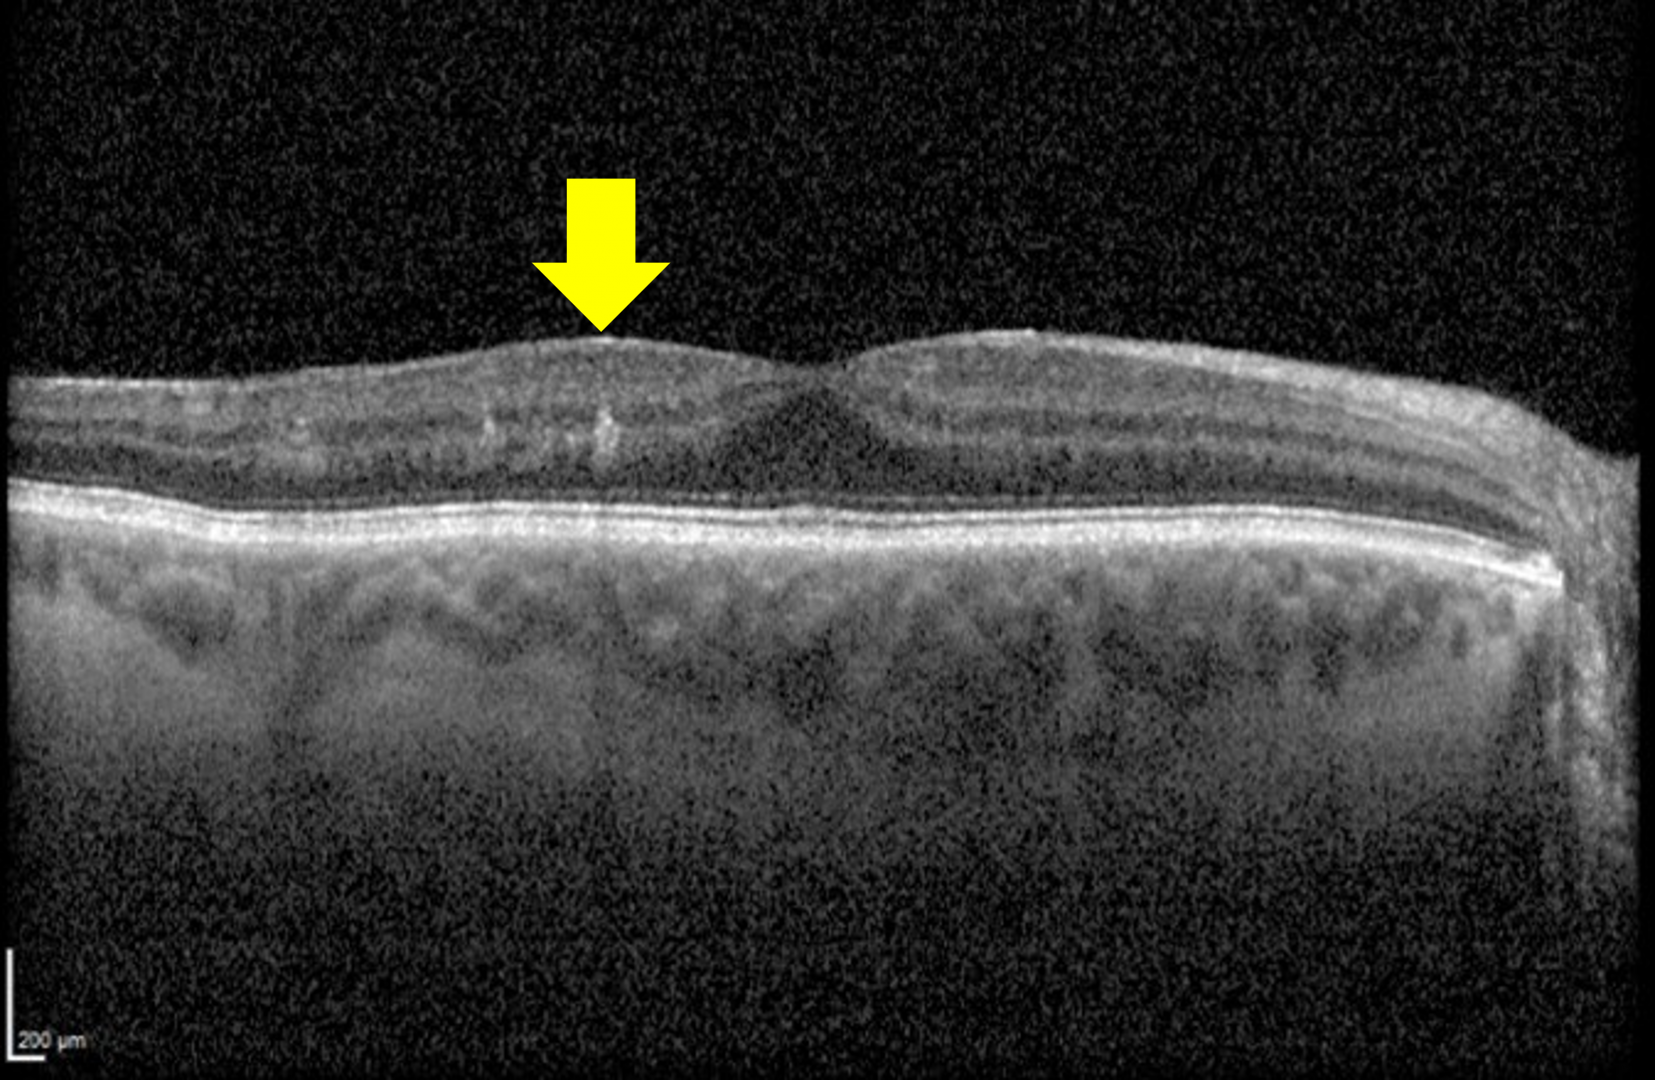

Recent studies have identified a clinical finding termed DRIL (disorganization of the retinal inner layers), which is used to describe poorly-defined boundaries of key inner retinal structures including the ganglion cell layer-inner plexiform layer (GCL-IPL) complex, inner nuclear layer (INL), and outer plexiform layer (OPL).

DRIL affecting more than 50% of the central 1-mm area of the retina is considered clinically significant. DRIL typically occurs in the central subfield of the ETDRS grid, and studies have shown that a 300 µm increase in DRIL is associated with a 1-line reduction in acuity.

The presence of DRIL has high diagnostic accuracy for identifying areas of non-perfusion (sensitivity 84.4%, specificity 100%). It is important to note however that not all areas of non-perfusion show signs of DRIL.

Spectralis OCT line scan (left macula)

More info